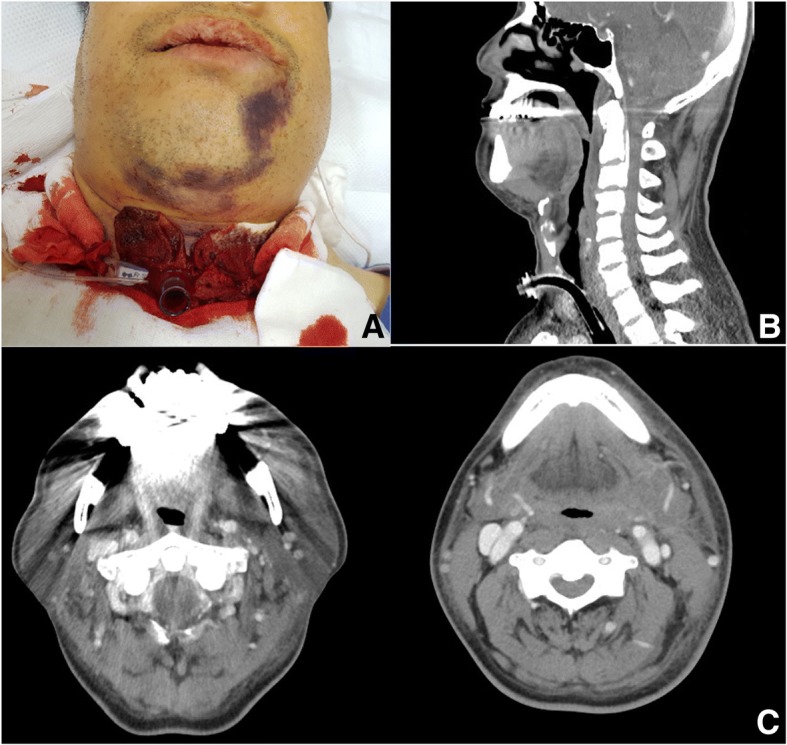

One month after the extraction, the patient underwent dental implant surgery at the same site (the left mandibular first molar) at the same local dental clinic. Bleeding started immediately after fixture installation and the mouth floor began to swell. Therefore, the patient visited the emergency room (ER) of the authors’ hospital. The patient was prescribed medication to control hypertension but no medication for ITP. The patient complained of severe swelling on the mouth floor and shortness of breath accompanied by marked dysphagia, which had also occurred immediately after the surgery. Bilateral submandibular swelling and mouth-closing difficulty were present (Fig. 1).

Fig. 1.

a Facial swelling of an emergency room arrival. b Intra-oral view: mouth floor elevation and bleeding at the implantation site. c CT axial view showed severe narrowing pharyngeal airway due to soft tissue swelling in the left masticatory, mandibular spaces, hypopharynx

Facial-enhanced computed tomography revealed severe narrowing of the pharyngeal airway space. Marked soft tissue swelling was observed with isodensity in the left masticatory and submandibular spaces and hypopharynx. The patient complained of worsening respiration in the ER. The expanding hemorrhage was deemed to potentially result in a compromised airway with a life-threatening outcome. Therefore, the surgical wound from the dental implant was opened to evacuate the hematoma and an emergency tracheostomy was performed under local anesthesia and intravenous sedation to maintain airway patency. The patient was then admitted to the intensive care unit (ICU).

Laboratory data after 3 days in the ICU showed a platelet count of 129,000/μL and other complete blood count (CBC) values within normal ranges. Follow-up CT 3 days later revealed that the hemorrhage had not expanded further. Moreover, diminished soft tissue swelling was noted along the superficial and deep neck spaces compared with the swelling shown on the previous CT images (Fig. 2). Therefore, the patient was extubated without dyspnea. The patient showed resolution of the mouth floor swelling, and no additional bleeding was detected; thus, he was discharged 9 days after admission.

Fig. 2.

a Constant bleeding at the tracheostomy site after an emergency tracheostomy. b Follow-up sagittal CT view and c axial CT views after 3 days showed decreased soft tissue swelling along the superficial and deep neck spaces at 3 days after tracheostomy